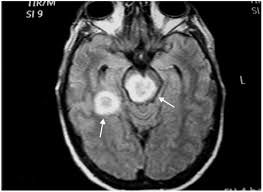

Meningoencefalitis, okužba osrednjega živčevja

Meningoencefalitis prizadene osrednje živčevje .

Pri nas, pa tudi na širšem območju regije je meningoencefalitis resen zdravstveni problem . Pomembnost problema je v pogostosti, možnih posledicah ter resnosti bolezni. Meningoencefalitis je sezonska težava. Ta značilnost, ki jo ima meningoencefalitis izvira iz biološke aktivnosti klopov. Ti so življenjsko najbolj aktivni v toplejših delih leta.

Aktivnost klopov začne z pomladansko otoplitvijo. Ugodne življenjske razmere začnejo, ko se temperatura tal dvigne nad pet stopinj Celzija. Preko statističnih podatkov pa ugotovimo, da je najverjetnejši čas okužbe v poletnih mesecih. Torej julija in avgusta. Redkeje je meningoencefalitis težava v zimskih mesecih. Klop v tem odboju leta prezimuje. Izjema so ugodni življenjski pogoji. Takšni pogoji nastopijo v hlevih, kjer so pogoji za aktivnost klopa ugodni tudi novembra ali decembra. Poleg tega so za preživetje klopov v zimskih mesecih ključne mile zime. Klop potrebuje za preživetje ugodne temperature, ni ne smejo segati bistveno pod ničlo. Največkrat si poišče zavetje, v katerem mu je omogočeno vzdrževanje minimalnih življenjskih pogojev. Od leta do leta je razvoj klopa v času, ko se otopli zelo različen. Najbolj ugodni pogoji nastopijo v primerih, ko so pomladni meseci vlažni. Klop namreč potrebuje vlažna okolja, da se lahko razvija in obstoji. V nasprotnem primeru se posuši in umre. Zato se tudi naseli povsod tam, kjer je dovolj vlage. Poleg tekočih in stoječih voda, so idealni pogoji na travnikih in v godovih. Virus meningoencefalitis se prenaša preko okuženih klopov. Vsi klopi niso okuženi.

Njihova okužba je možna na dva osnovna načina. Problem, ki ga predstavlja okužba je njeno trajno učinkovanje. Okužen klop lahko virus prenaša celo življenje. Klop za razvoj potrebuje kri gostitelja. Za človeka je najbolj kritičen začetek prenosa. Slina klopa ima v sebi snovi, ki pri človeku zmanjša bolečino ob ugrizu. Meningoencefalitis tako začne svoj prenos praktično brez bolečine, kar mnoge osebe zavede.